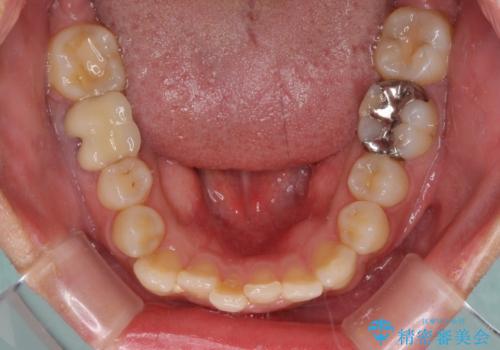

前歯のデコボコとクロスバイト インビザラインによる矯正治療

- 上下のクロスバイトと前歯のデコボコを気にして来院された患者様です。

骨格的に下顎がやや前方にあり、奥歯にクラウンが装着されているため、矯正治療後半の不安定な咬み合わせを避けるのであればワイヤー矯正がおすすめとなりますが、希望によりインビザラインにて治療を行うこととしました。

インビザラインを用い、IPR(歯と歯の間を削る)と歯列全体を拡大させることで、歯並びを整えていくこととしました。

懸念されたとおり、右下のクラウン部分が全く咬み合わず、仕上げの段階で治療期間が長くなりました。